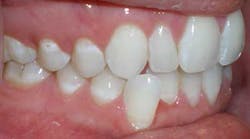

As noted above, the patient had a retained primary molar. Since the primary molar had larger mesial-distal dimensions than a second premolar, the completed treatment resulted in an acceptable compromise of interdigitation on this side. Treatment progressed very well, although a refinement was needed to finish the positioning of the lower right cuspid at the end of treatment (Figs. 9-16). The patient was given final upper and lower in-house thermoformed retainers to wear at night. Then a few months later, a permanent lingual retainer was bonded at the patient’s request on the lower from cuspid to cuspid.

Figs. 9-16